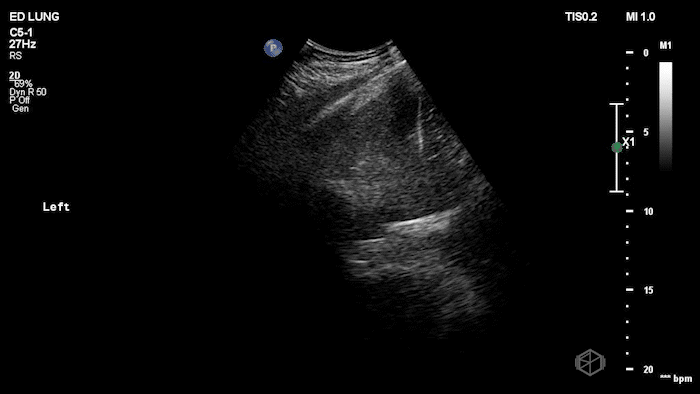

The next SonoProps goes to Dr. Jaspreet Kaur and Dr. Obioma Nkemakolam. They were scanning a late 80s male with a mechanical fall in the shower onto his left side, with significant left-sided ecchymosis. He was taking Xarelto. He was initially placed in a stable area of the ED. Dr. Kaur and Dr. Nkemakolam scanned the patient and found him to have the following clips:

The scan shows echogenic dependent pleural fluid above the diaphragm on the affected side. Fluid layering in a gravity-dependent region (posterior/lateral chest) consistent with pleural effusion in trauma = hemothorax until proven otherwise in a patient with no prior history of pleural effusions. The patient had normal lung sliding bilaterally indicating no pneumothorax. He was found to have 6 rib fractures on CT, but was otherwise stable and pain controlled, saturating well on room air.

Diagnosis: Left hemothorax with multiple rib fractures